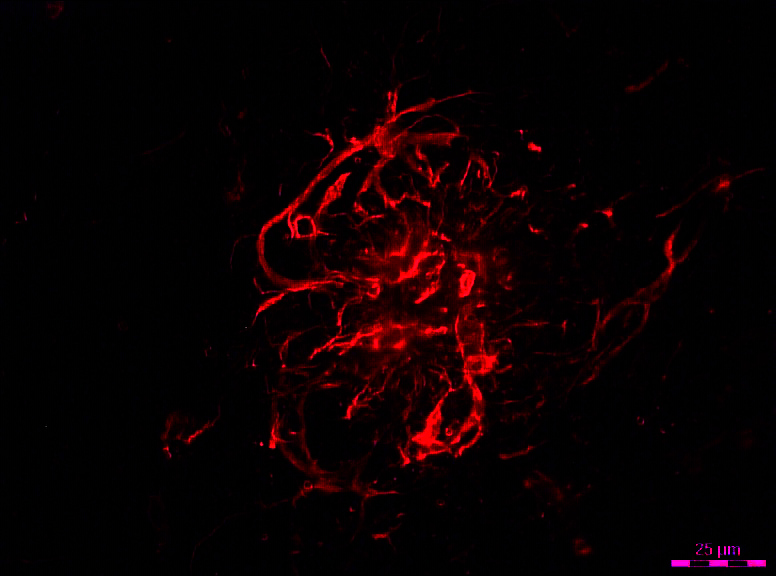

这里使用激光微粉切割以产生例如单个或几种相同类型的细胞特异性基因表达谱。激光微生物在神经科学中起着特殊作用,用于去除来自组织的个体神经元,特别是将它们与周围的胶质细胞分离。该技术同样成功地精确地切割轴突或解剖突触。

在多巴胺的研究中,重点是中脑产生多巴胺神经元的基因表达分析。在帕金森病、精神分裂症、多动症和药物成瘾等疾病模式中,可以观察到所谓的多巴胺中脑系统的故障。当涉及进行性的、选择性的细胞丢失时,如帕金森病,健康和病变组织区域的单细胞的分解是必要的。

在这里,激光显微解剖使单个受影响的细胞从Imageia nigra.帕金森患者和来自非受影响的健康对照组织,以检测这些细胞基因表达的差异在发展疾病上。多巴胺能的基因表达Imageia nigra.也可以与来自邻近腹侧的多巴胺能神经元进行比较神经元,这些腹侧特子区域在Morbus帕金森的脆弱区内易受伤害,以便发现是什么使神经元易受伤害或更耐药。